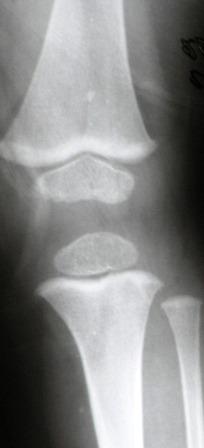

Уважаемые коллеги! Помогите уточнить диагноз. На ортопедический прием мама привела упитанного 3 летнего мальчика. Родился и рос нормальным ребенком. Последнее время стал жаловаться на ножки. Мама заметила Х-образную деформацию нижних конечностей. При осмотре отмечена легкая вальгусная деформация коленных суставов, плоскостопие. Предполагаю, что это МЭД - множественная эпифизарная дисплазия. Р-грамма прилагается. Какие варианты лечения?. С уважением Виктор

При более близком рассмотрении Рг создается впечатление неоднородности структуры зоны роста в латералных отделах дист. бедра при нормальной

структуре медиальной пластинки. Эпифизы, на мой взгляд, выглядят вполне симметричными и не измененными.

Уважаемый Евгений! Спасибо за обстоятельный совет. Обязательно сделаю КТ или МРТ. Неоднородность структуры зоны роста я, к сожалению, не заметил. По-моему, возникают ассоциации с механизмом развития избыточной антеверсии шейки бедра. Но, все-таки у меня остается впечатление «сжатости» метафизов, особенно бедра.

Для иллюстрации привожу пример из «Нормальной рентгеноанатомии костно-суставной системы детей». В. И. Садофьева. ЛЕНИНГРАД «МЕДИЦИНА» 1990

^^^^^^^^сурово ;) В любом случае одних снимков коленных суставов для такого вывода недостаточно. По снимкам- норма